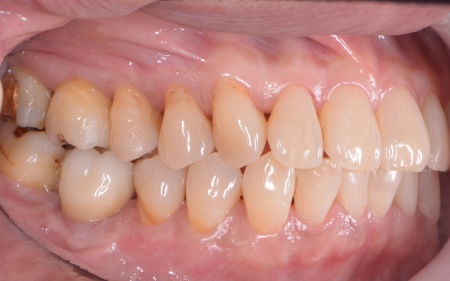

また、左上の奥歯は虫歯を取り除いたあと、歯の形を整えて型取りを行い、最終的にジルコニアクラウンを装着しています。

段階的に治療を進め、すべての治療を終了しました。

歯周組織再生療法4ヶ所、インプラント2本、角化歯肉移植、ジルコニアクラウン